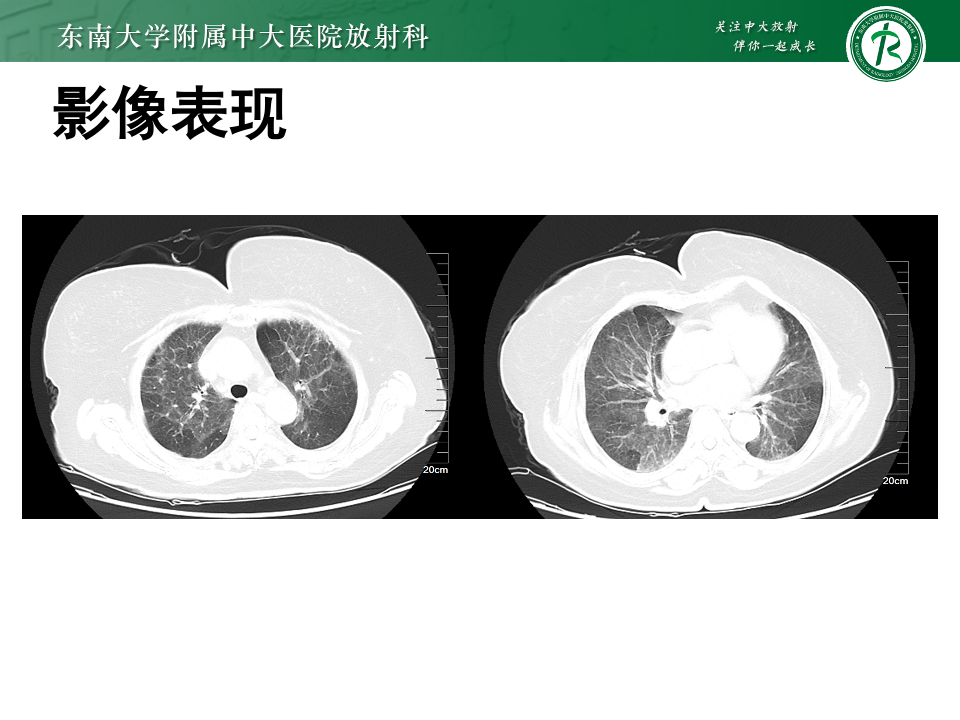

过敏性肺炎1例

• 女,65岁

• 主诉:反复胸闷气喘1年

• 现病史:现病史:患者一年前无明显诱因下出现胸闷、气喘,位于心前区,自觉压迫感,休息后缓解,伴活动后气喘,爬2楼气喘明显,无胸痛,无畏寒发热,患者症状改善不明显。

• 检查日期:2019/08/31

影像学表现